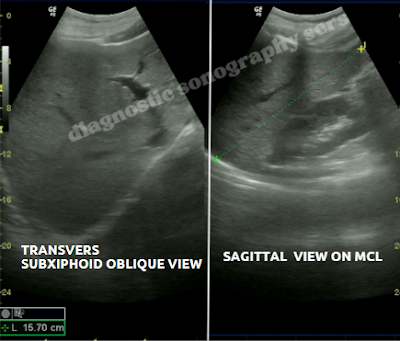

• Hepatomegaly: Measures liver size, contour, echotexture, and detects masses.

• Texture changes: Bright liver = steatosis; coarse = fibrosis or cirrhosis; focal lesions indicate masses.